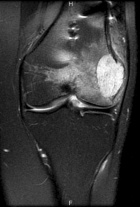

Patient is a 26 y/o male w/ hx. of polyostotic fibrous dysplasia s/p IM nailing for a pathologic L. femur fx. seven yrs. ago presents c/o 1 yr. hx. of increasing L. lat knee pain/swelling; PMH: polyostotic fibrous dysplasia and L. humerus fx; PE: L. knee w/ minimal effusion; +TTP over lat. condyle and w/ flexion to 100 deg; NVI